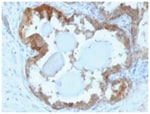

HSP27 Monoclonal specifically detects HSP27 in Human, Mouse, Rat, Chicken, Chimpanzee, Monkey, Sheep samples. It is validated for Western Blot, Flow Cytometry, Immunohistochemistry, Immunocytochemistry/Immunofluorescence, Immunohistochemistry-Paraffin.Specifications

| This MAb reacts specifically with heat shock protein HSP27 in human and monkey tissues and cell lines such as MCF-7. HSP27, also referred to as the Estrogen-Regulated 24K protein and HSP28, is one of several small heat shock proteins produced by all organisms studied. HSP27 synthesis is induced by elevated temperature, as well as by estrogen in hormone responsive cells. Interestingly, human HSP27 also shares greater than 50% homology with low molecular weight Drosophila HSPs and mammalian alpha-crystalline lens protein. Because of the estrogen responsive nature of HSP27, this protein has been studied extensively in human estrogen responsive tissues such as cervix, endometrium and breast tissue. Therefore HSP27 may be useful in classifying various hormone sensitive tumors. |